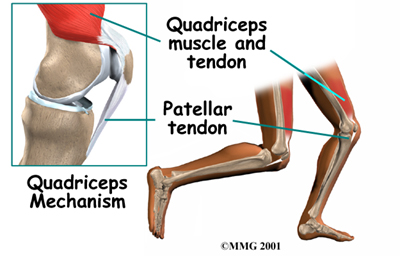

The patella (kneecap) is the moveable bone on the front of the knee. This unique bone is wrapped inside a tendon that connects the large muscles on the front of the thigh, the quadriceps muscles, to the lower leg bone. The large quadriceps tendon together with the patella is called the quadriceps mechanism. Though we think of it as a single device, the quadriceps mechanism has two separate tendons, the quadriceps tendon on top of the patella and the patellar tendon below the patella.

The patella (kneecap) is the moveable bone on the front of the knee. This unique bone is wrapped inside a tendon that connects the large muscles on the front of the thigh, the quadriceps muscles, to the lower leg bone. The large quadriceps tendon together with the patella is called the quadriceps mechanism. Though we think of it as a single device, the quadriceps mechanism has two separate tendons, the quadriceps tendon on top of the patella and the patellar tendon below the patella.

Tightening up the quadriceps muscles places a pull on the tendons of the quadriceps mechanism. This action causes the knee to straighten. The patella acts like a fulcrum to increase the force of the quadriceps muscles.